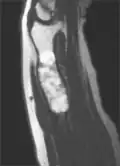

MRI showing enchondromas localized in the lower part of the radius of a 37-year-old patient affected with Ollier disease -

MRI showing enchondromas localized in the lower part of the radius of a 37-year-old patient affected with Ollier disease. -